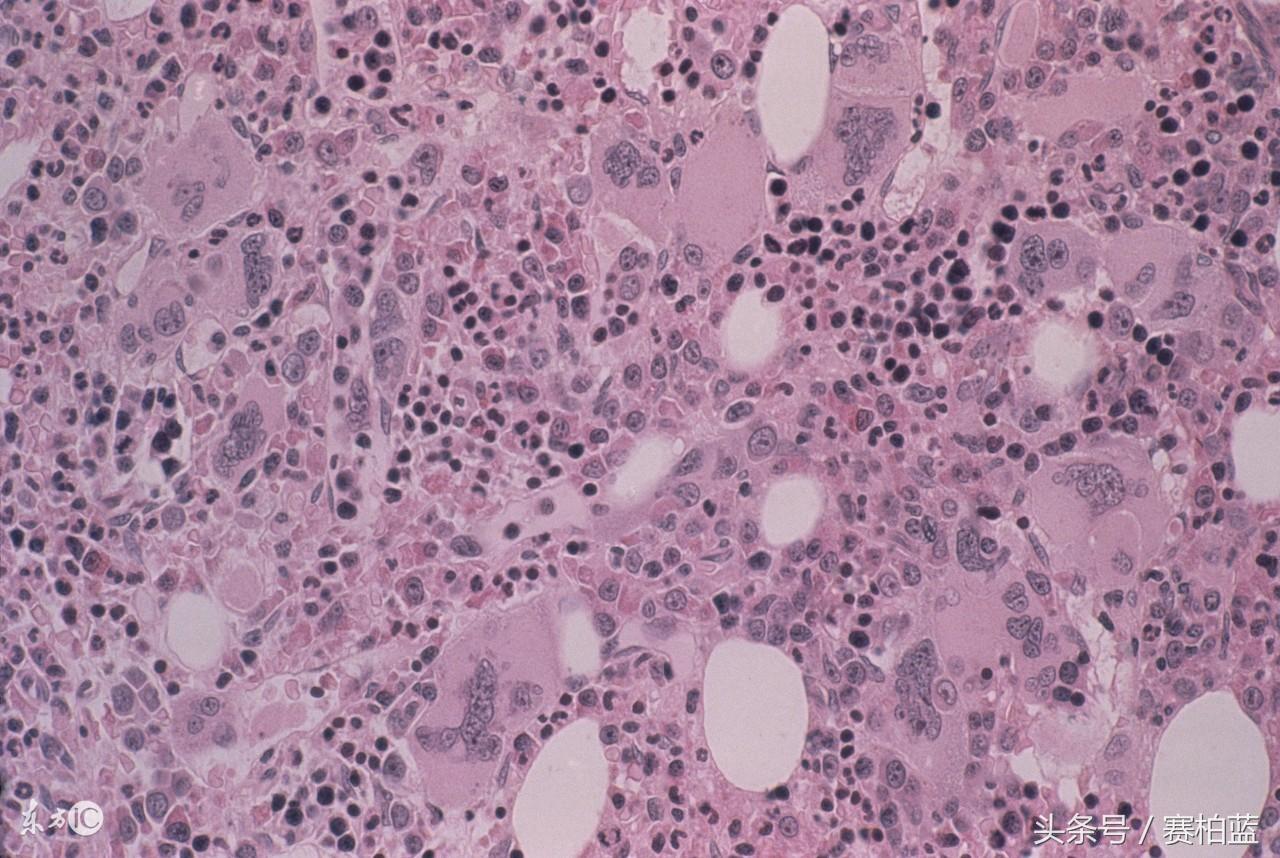

二、肝纤维化——–肝病进展的命脉

肝纤维化是慢性肝病进程中相当重要的一环。肝脏一旦发生纤维化,如同一只脚迈进了肝硬化的门槛,将无法逆转。

1.应对措施:补充硒

体内缺硒的人容易被肝炎病毒传染,补硒后肝纤维化程度明显缓解。硒还能有效改善肝病,预防肝癌?;加新愿窝?、脂肪肝、酒精肝的人士都应当补充硒。